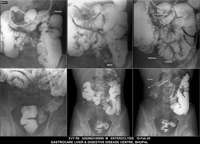

Section: ENTEROCLYSIS

Total: 205 Cases